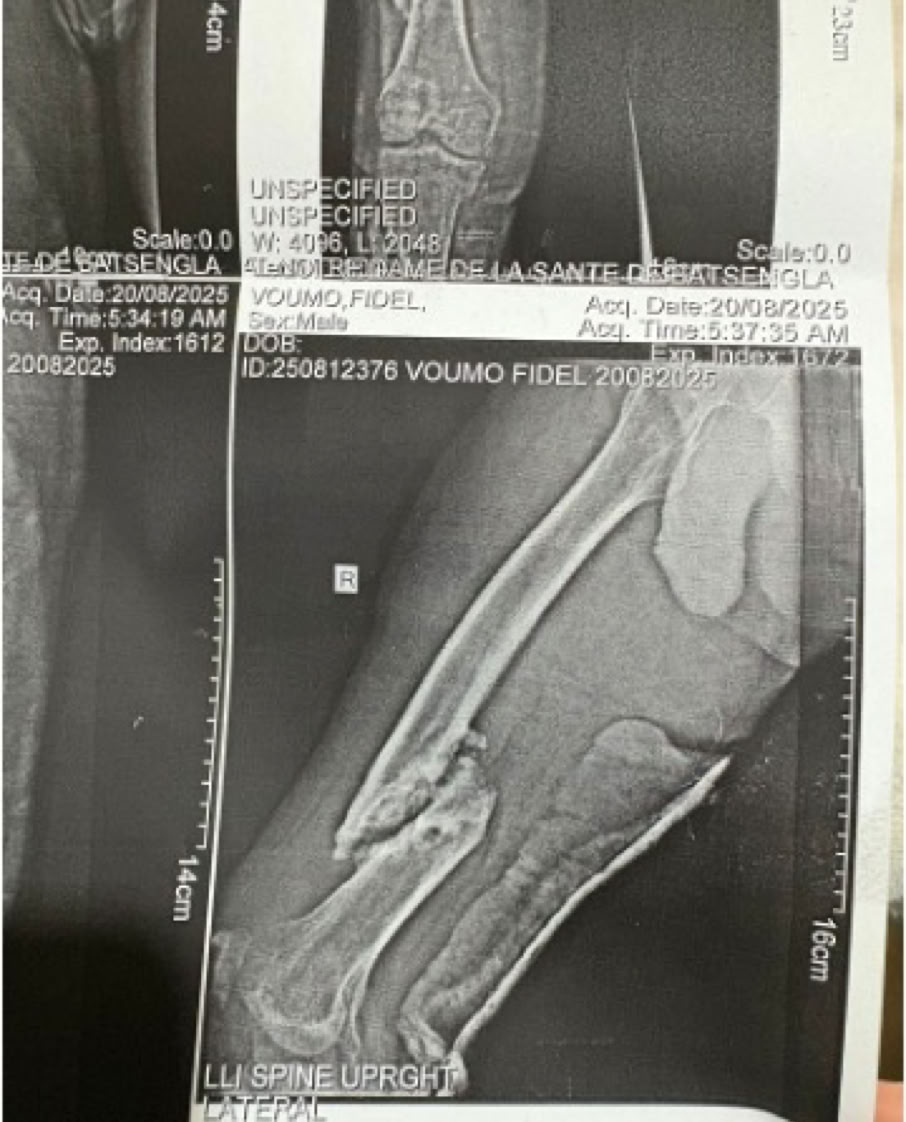

Nos encontramos dos casos de rodillas flotantes que pudimos resolver y casos de retardo de consolidación e infecciones de intervenciones previas. Igualmente las osteomielitis hematógenas y las sécales de la diabetes ocupa gran parte de la actividad de consultas de sala de curas y de las sesiones quirúrgicas.

A partir del lunes y tras la oración de bienvenida al inicio de la jornada en la que nos fuimos presentando todos los componentes de la expedición, las tareas asignadas se fueron distribuyendo entre la consulta, las dos salas de Curas y los dos quirófanos, que además se han mantenido activos todos los días de la semana en turnos de mañana y tarde con cirugías complejas en ambos. Esto nos ha permitido por ejemplo abordar principalmente enclavados de fémures y tibias y también casos de luxaciones inveteradas de hombro y de tobillo.

Como en expediciones anteriores, las complicaciones de cirugías previas en otros centros, la demora de los tratamientos por el empleo de la medicina tradicional (masajes) mencionada antes, y la elevada tasa de infecciones tanto hematógenas como secundarias a diabetes mal controlada o sin tratamiento, han ocupado gran parte de nuestro trabajo.

Los accidentes de tráfico, o de moto en su casi totalidad, como mecanismo de producción nos da una idea de la alta complejidad de los pacientes que han ocupado nuestra labor diaria, labor que hemos llevado a cabo mano a mano con el equipo local, al que vemos en cada expedición tener una mayor autonomía, experiencia técnica y profesionalidad. Hemos echado de menos al  Dr. Yannick que se ha marchado a Francia para hacer su especialización, confiemos en que vuelva. Si hemos podido compartir cirugías y consultas con los doctores Emmanuel y Ármel viendo como van aumentando su experiencia.